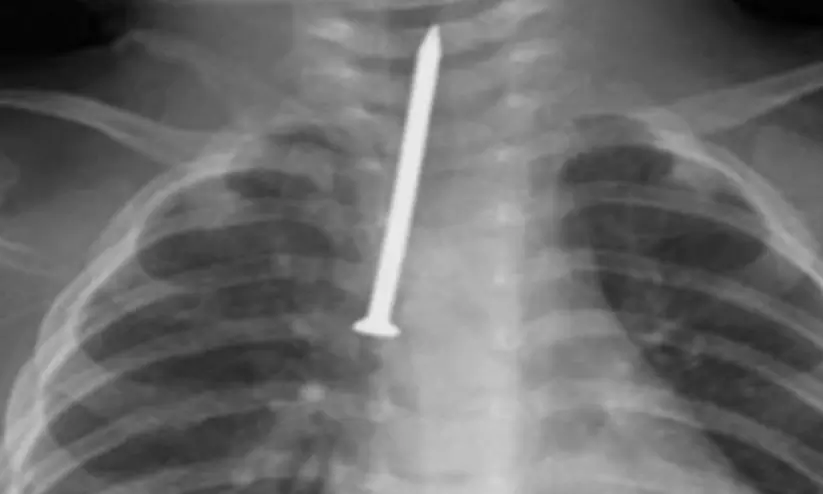

അപ്രതീക്ഷിതമായി കുഞ്ഞ് ആണി വിഴുങ്ങുകയും അത് ശ്വാസനാളത്തിൽ തടയുകയുമായിരുന്നു. അഞ്ച് സെൻറീമീറ്റർ നീളമുള്ള ആണി പ്രധാന ശ്വാസകോശ കുഴലിലേക്ക് കടന്നതോടെ കുഞ്ഞി​െൻറ നില അതീവ ഗുരുതരമായി. തുടർന്ന് ഒട്ടും വൈകാതെ തന്നെ കുഞ്ഞിനെ ഓപ്പറേഷൻ തിയേറ്ററിലേക്ക് മാറ്റുകയും ‘റിജിഡ് ബ്രോങ്കോസ്കോപ്പി’ എന്ന അത്യാധുനിക എൻഡോസ്കോപ്പി സംവിധാനം ഉപയോഗിച്ച് ആണി പുറത്തെടുക്കുകയുമായിരുന്നു.

കുഞ്ഞിന് കഠിനമായ ശ്വാസതടസ്സം നേരിട്ടിരുന്നതായും വലിയൊരു വസ്തു ശ്വാസനാളത്തിൽ കുടുങ്ങിയതിനാൽ വലിയ അപകടസാധ്യത നിലനിന്നിരുന്നതായും തൊറാസിക് സർജറി വിഭാഗം മേധാവി ഡോ. മുഹമ്മദ് അൽ അംസി പറഞ്ഞു.